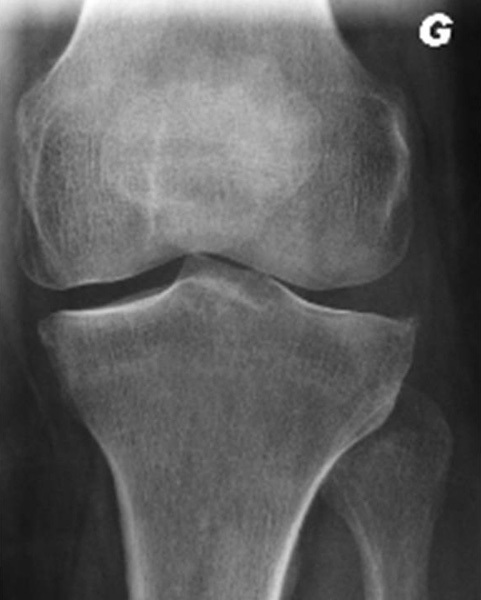

Ostéophytose du genou gauche

Gonalgie gauche interne avec ostéophytose sans pincement du compartiment fémoro-tibial interne.